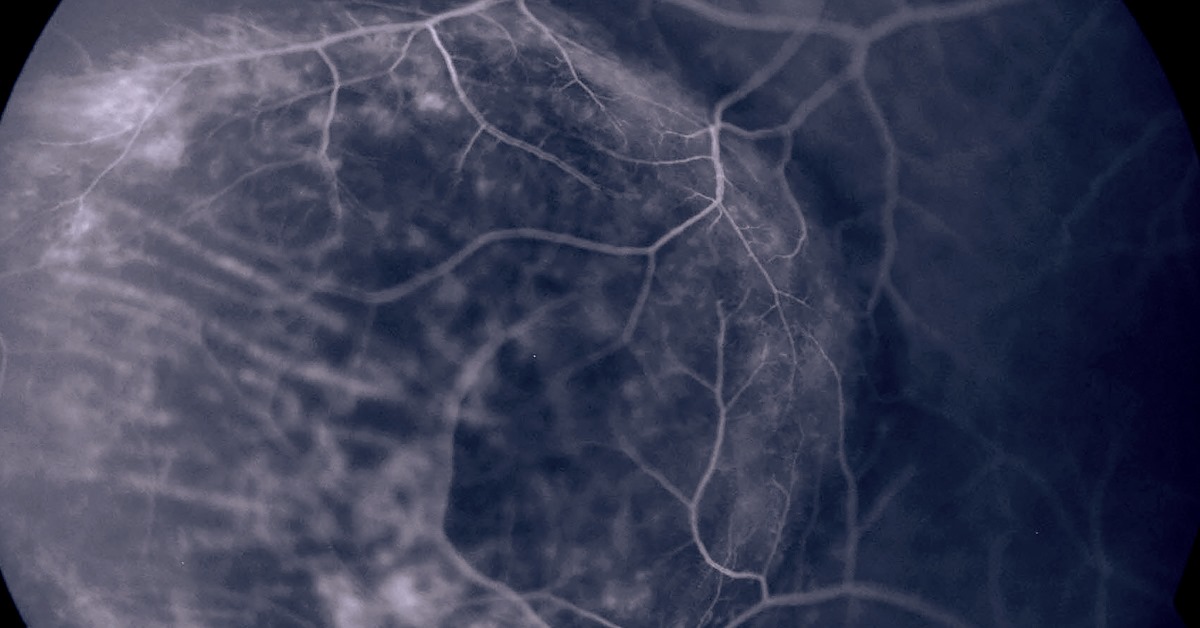

Lattice Degeneration is a thinning of the Retina that happens over time. Although 10% of the population has Lattice Degeneration, most will not have any symptoms or loss of vision as a result. Rarely, Lattice Degeneration may lead to Retinal Detachment. While doctors aren’t certain about what causes Lattice Degeneration, it’s most common in people with myopia, or nearsightedness, and in people with diseases like Stickler or Marfan syndrome. Although it is not genetically passed down from parents, those with a family history are more likely to also contract it. Lattice Degeneration doesn’t typically have symptoms, but because the Retina is thinner it is more subject to holes, tears, and breaking, which can in turn lead to Retinal Detachment, which can cause blindness if not treated immediately. Learn more about Lattice Degeneration at https://bit.ly/3gE9BM6